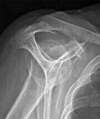

Volumineuse calcification tendineuse

- Des radiographies qui permettent de retrouver des signes indirects de tendinopathie sur le trochiter, un acromion trop plongeant ou une arthrose acromio-claviculaire.